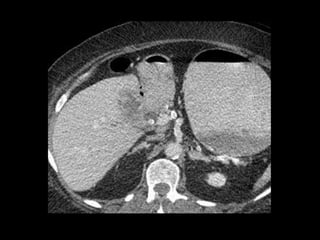

This document describes four patient cases seen by different doctors, including a 72-year-old female with abdominal pain, a 42-year-old female with abdominal pain and bloody diarrhea, a 37-year-old male with chest pain and vomiting of digested blood, and a 67-year-old male with an abnormal heart ultrasound.